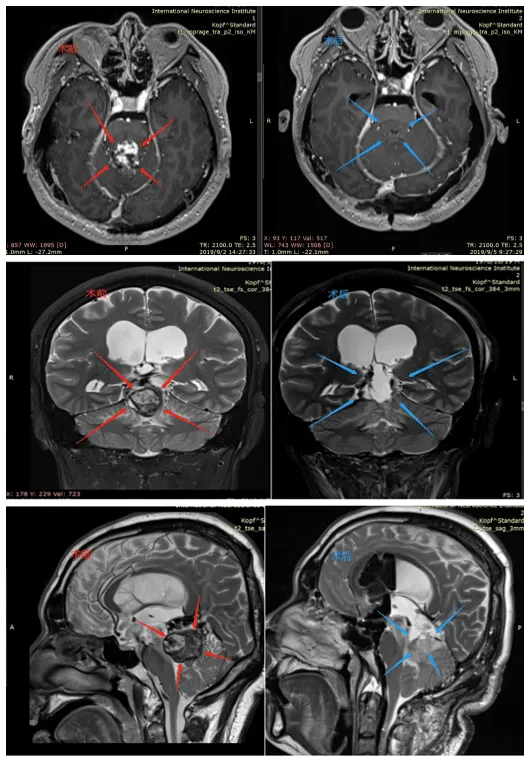

术前MRI(红色标记):松果体区占位病变,考虑肿瘤性病变,可见强化信号,侵犯压迫第四脑室,伴脑干水肿

术后3天MRI(蓝色标记):松果体肿瘤完全切除,无残留病灶,无神经功能损伤(病灶区异常信号为手术止血材料)

术后情况:术后第2天拔除气管插管,自主呼吸正常,生命体征稳定,转出ICU,复视症状改善;术后5天在专业人员协助下床康复训练,头晕明显减轻,肌力恢复;术后18天顺利出院,无新发神经功能缺损